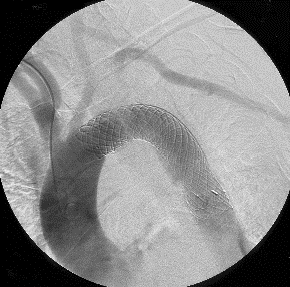

ステントグラフト

ステントグラグト挿入術:レントゲン透視下に実施

胸部大動脈瘤のステントグラフト治療